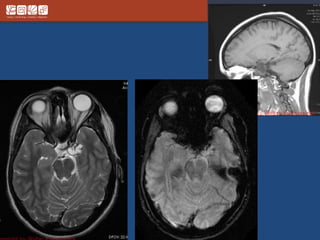

Pituitary Macroadenoma

• Usually soft

• Elevate diaphargma selle

• Often contrasted at diaphargmatic hiatus as

tumor growth into the suprasellar cistern

• Snowman shape

• *commonest large tumor of the skull base